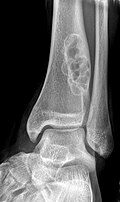

===Radiology===

*Sharply demarcated, lucent, loculated, meta-diaphyseal lesion.

*Surrounded by a rim of sclerotic bone.

==Radiographic findings==

Sharply demarcated, lucent, loculated, meta-diaphyseal lesion surrounded by a rim of sclerotic bone

• Sharply demarcated, lucent, loculated, meta-diaphyseal lesion.

• Surrounded by a rim of sclerotic bone.